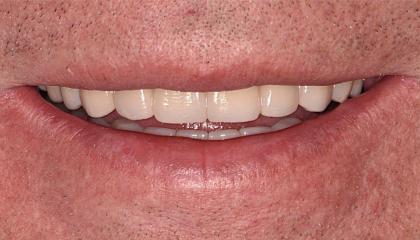

After